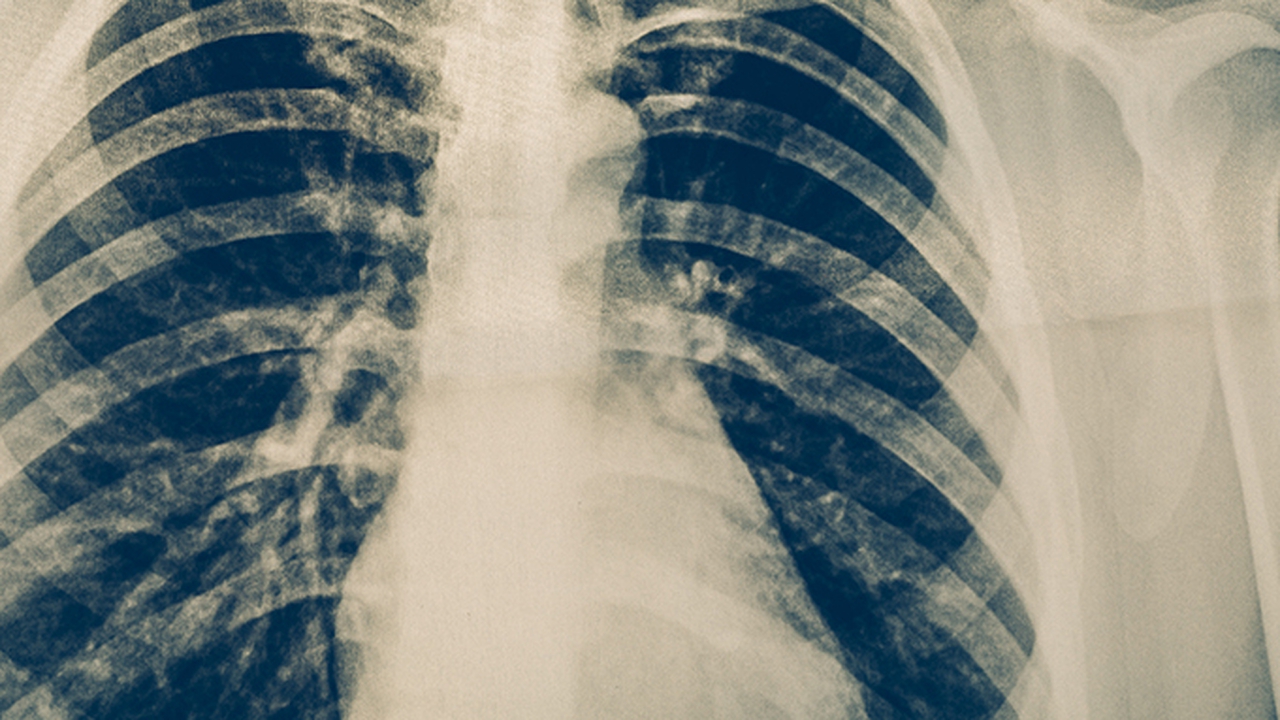

肺癌作为高发恶性肿瘤,其治疗需要多学科协作,涉及手术、放疗、化疗及靶向治疗等多种手段。南京作为医疗资源丰富的城市,拥有多家在肺癌诊疗领域具有较高水平的医院,可为患者提供规范化、个体化的治疗方案。

肺癌的预防与健康管理至关重要,长期吸烟、空气污染、职业暴露等因素均可能增加肺癌风险。建议高危人群定期进行低剂量螺旋CT筛查,早期发现可显著提高率。此外,保持健康生活方式,如戒烟、均衡饮食、适度运动,有助于降低肺癌发病风险。对于已确诊患者,应积极配合医生治疗,并定期随访,以提高生存质量。